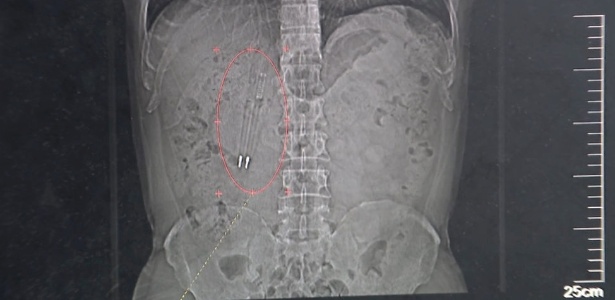

Conforme a publicação, o homem identificado como Wang esqueceu das canetas e achava que seu corpo teria expelido. Ele ficou surpreendido depois que viu o exame de raio-X. Após o susto, ele se recuperou bem da cirurgia.